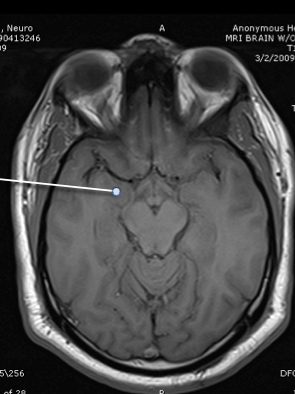

amygdala

hypothalamus

hippocampus